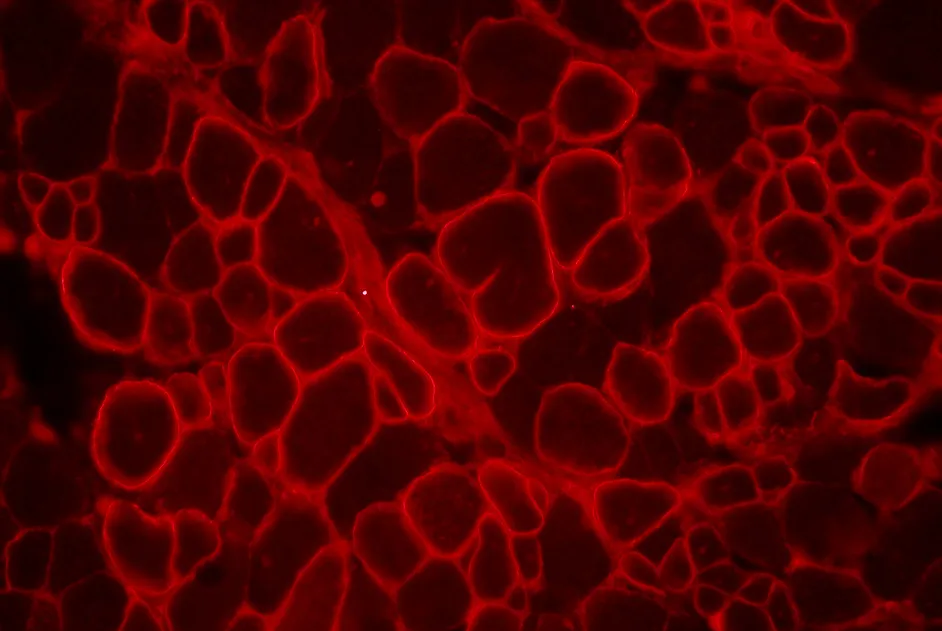

Preuve de concept de la faisabilité d’une modification du génome pour améliorer le phénotype de cellules souches atteintes de DM1.